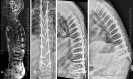

Methods: We report 2 unique cases of distal junctional failure (DJF) with worsening of neurology, secondary to nontraumatic fracture of a lower instrumented vertebra operated for thoracic canal stenosis without deformity. The first case had acute worsening of the Neurology during follow up and on evaluation, the supine CT and MRI scan revealed well decompressed spinal canal, no implant migration to the canal, no screw loosening, or rod failure. Supine sitting radiographs demonstrated DJK with Fracture and the patient underwent extension of fusion till the pelvis with 3-rod construct and interbody fusion, because of the instability at the L1 level.The second case remained neurologically stable for a month and then had an acute onset of back pain, sensory deficit, and urine incontinence. The supine-sitting dynamic radiograph done demonstrated L1 fracture with DJK at D12-L1 levels. The patient was counseled for extension of fusion, which was deferred by the patient.

Results: Patients in our series, had an acute worsening of neurological deficit within a month of posterior spinal fixation. Their supine imaging was almost normal, and the diagnosis of DJK with L1 fracture instability was possible only on a supine-sitting dynamic radiograph. Various factors like obesity, TL kyphosis, osteoporosis, etc. can be the attributing factors for the development of DJK CONCLUSION: A high index of suspicion is required for diagnosing nontraumatic fracture in long-level fusion patients with acute neurological worsening. The supine-sitting dynamic radiograph is an important diagnostic tool for DJF in patients having difficulty standing erect.